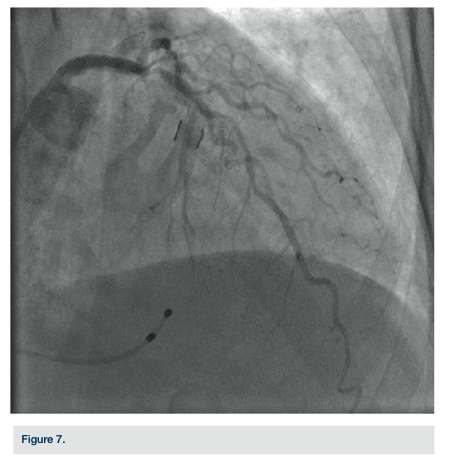

The right radial artery was prepped and draped in sterile fashion, then accessed with a 6 French (Fr) Glidesheath (Terumo). The right antecubital vein was accessed by the nurse prior to the patient’s arrival to the lab and changed (after sterile prep followed by betadine solution) to a 5 Fr Glidesheath (Figure 2). The transvenous pacemaker was advanced  into the right ventricle (Figure 3). Following placement of the pacemaker and capture, a Judkins right (JR) 4 6 Fr guide was used to engage the right coronary artery. Angiography demonstrated a proximal right coronary artery occlusion with TIMI-0 flow (Figure 4). After administration of bivalirudin (Angiomax, The Medicines Company), a Runthrough wire (Terumo) was passed distally. A 1.0 x 10 mm ClearWay balloon (Atrium Medical) was advanced to the lesion and intracoronary abciximab (ReoPro, Eli Lilly & Co.) was administered. Following drug administration, there was improved flow and evidence of a more focal obstruction (Figure 5). A 3.0 x 15 mm Integrity bare metal stent (Medtronic) was deployed at 11 atm with no angiographic residual stenosis and restoration of TIMI-3 flow (Figure 6).  Following revascularization of the right coronary artery, the guide was advanced into the left ventricle to calculate the left ventricular end diastolic pressure (LVEDP) and perform ventriculography (estimated ejection fraction was 55% with mild inferobasal hypokinesis noted on hand injection.  No significant transvalvular gradient was noted on pull-back). A diagnostic Judkins left (JL) 3.5 catheter was then used to engage the left coronary system. Angiography revealed a 90% proximal left anterior descending coronary artery (LAD) stenosis and intermediate disease of the circumflex (Figure 7).  The patient was started on ticagrelor (Brilinta, AstraZeneca) and aspirin, and transferred to the unit. The pacemaker was removed after the patient regained sinus rhythm. She was discharged home after 48 hours with plans for staged intervention of the LAD.